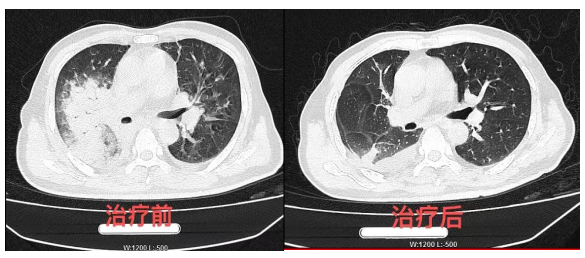

转科后,医生考虑患者系重症肺炎,予以抗感染、无创呼吸机辅助通气治疗,但患者咳嗽、发热及活动后气促症状无明显改善,随访血气分析提示氧合指数进行性下降,最低时氧合指数仅80左右。因患者病情危重,科室主任、副主任医师周雨在查房评估病情并与患者家属充分沟通后于4月8日行气管插管、有创呼吸机辅助通气治疗,复查胸部CT提示肺部炎症较前进展,胸腔积液也较前增多,遂立即行纤维支气管镜检查留取肺泡灌洗液送检mNGS,4月10日肺泡灌洗液mNGS结果提示:检测出鹦鹉热衣原体,序列数2078。科室立即调整为多西环素联合莫西沙星继续抗感染,继续有创呼吸机机械辅助通气,并辅以俯卧位通气、纤支镜床旁灌洗等治疗,患者体温逐渐控制,复查胸部CT提示肺部病变逐渐吸收,血气分析提示氧合指数逐渐上升至300左右,于4月19日顺利拔管、停用有创呼吸机,予以序贯脱机治疗。4月29日复查胸部CT提示右肺病变明显吸收,胸腔积液减少,患者在不吸氧情况下已能自理生活,无明显活动后的气促表现。患者于4月30办理出院并口服抗感染药物以继续治疗。患者及其家属对该科的治疗效果非常满意,特亲笔书写感谢信对科室主任周雨及全科医务人员表达最诚挚的谢意。